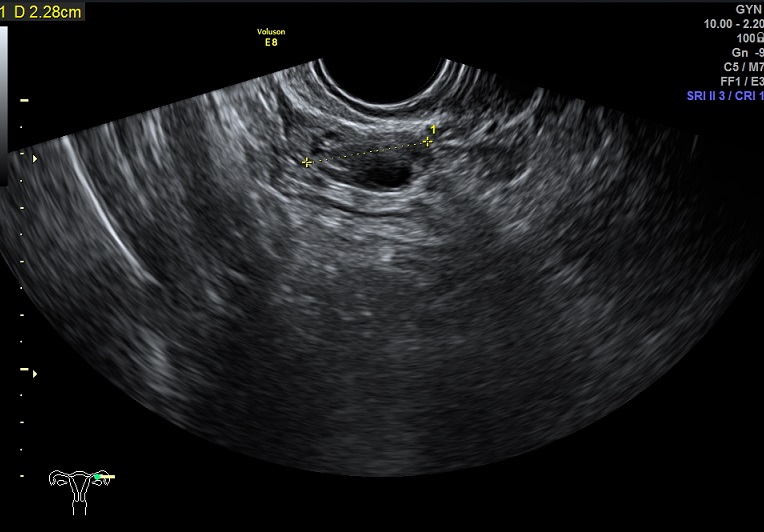

女性,27岁,原发性不孕。

2015-1-12,月经第3天检查

左卵巢: 大小2.9x2.3x1.4cm 体积:4.8 窦卵泡:4个 卵巢间质血流:9.8cm/s RI:0.49

右卵巢: 大小 2.6x1.6x1.3cm 体积:2.8 窦卵泡:2个 卵巢间质血流:11.5cm/s RI:0.52